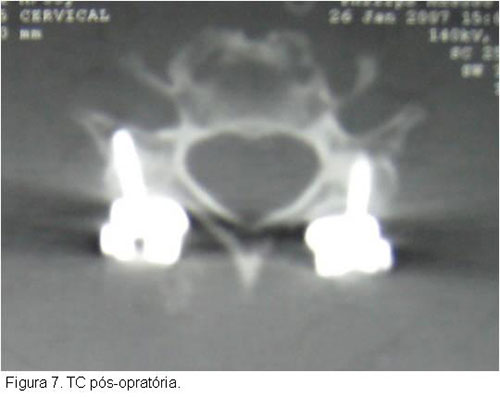

O tratamento cirúrgico tem se beneficiado muito das inovações tecnológicas que propõem cada vez mais técnicas mais rápidas, seguras e com maior poder de estabilização da lesão óssea.O tratamento farmacológico restringe-se a corticoterapia a fim de evitar lesões secundárias, porém novas drogas estão sendo testadas e poderão ser introduzidas num futuro próximo, como o gangliosídeo.O tratamento biológico consiste na maior esperança para o lesado medular, a expectativa de que o uso de células tronco possa proporcionar uma restauração da via neurológica acometida no trauma, vem estimulando diversas pesquisas nesta direção, entretanto ainda estamos em fase inicial desta metodologia.Já a terapia por meios físicos, como a câmara hiperbárica, não demonstrou benefícios nos ensaios animais (figuras 2, 3, 4, 5, 6, 7).